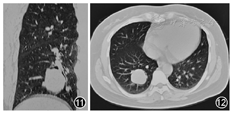

患者45岁,女性,既往体健。因"记忆力减退、精神异常3个月"余于2018年5月25日入滨州医学院附属学院。患者于2018年2月14日无明显诱因出现记忆力减退,表现为近期事件遗忘,反应尚可,可正常交流,2月16日后出现情绪不稳定,烦躁不安,时有喊叫及自言自语,交流困难,睡眠障碍,当时测体温38 ℃,遂就诊博兴县人民医院,颅脑MRI提示双侧海马硬化(图1,图2,图3,图4),血常规:嗜酸细胞百分比0%,单核细胞计数0.73×109/L,嗜酸细胞计数0×109/L,余未见明显异常。未予治疗,由于上述症状持续存在,于2月18日就诊胜利油田中心医院,行颅脑MRI+磁共振波谱(MRS)示双侧海马FLAIR信号增高,不除外海马硬化;MRS示左侧海马N-乙酰天冬氨酸(NAA)减低,NAA/肌酐、NAA/肌酐+胆碱比值降低。腰椎穿刺:颅内压190 mmH2O(1 mmH2O=0.009 8 kPa),脑脊液常规:无色透明,无凝块,潘氏蛋白定性(-),白细胞计数3×106/L,白细胞单核100%。脑脊液生化:蛋白0.41 g/L,葡萄糖3.8 mmol/L,氯化物122.3 mmol/L,腺苷脱氨酸0.3 U/L。新型隐球菌涂片、抗酸杆菌涂片阴性。脑脊液神经系统副肿瘤综合征系列:阴性。脑脊液自身免疫性脑炎系列:N-甲基-D-天冬氨酸受体(NMDA)型抗体、α-氨基-3-羟基-5-甲基-4-异恶唑丙酸(AMPA)1型抗体、AMPA2型抗体、抗富亮氨酸胶质瘤失活蛋白抗体、抗接触蛋白关联蛋白2(CASPR2)、抗GABAB受体抗体IgG阴性。血清自身免疫性脑炎系列:NMDA型抗体、AMPA1型抗体、AMPA2型抗体、抗富亮氨酸胶质瘤失活蛋白抗体、抗CASPR2、抗GABAB受体抗体IgG阴性。血清肿瘤标志物:鳞状细胞癌相关抗原、胃泌素释放肽前体、糖链抗原、神经元特异性烯醇化酶、细胞角蛋白19片段、甲胎蛋白、癌胚抗原、异常凝血酶原在正常范围,糖链抗原72-4 16.24 U/ml(高于正常值)。血常规:嗜酸细胞百分比0.3%,单核细胞计数0.64×109/L,余未见明显异常。诊断:病毒性脑炎、双侧海马硬化。给予阿昔洛韦、奥拉西坦治疗15 d出院,出院时无发热,情绪较稳定,仍近记忆力减退。5月15日受惊吓(打雷)后再次出现烦躁不安、时有吵闹,胡言乱语,无法交流,夜间不眠,测体温38.6 ℃,再次就诊博兴县人民医院,行颅脑CT未见异常,血常规示中性粒细胞百分比75.6%,淋巴细胞百分比19.1%,嗜酸性粒细胞百分比0.3%,余无异常,未予治疗。后再次就诊胜利油田中心医院,颅脑MRI+增强示双侧颞叶海马区斑片状长T2高信号,弥散加权成像(DWI)异常信号;增强后未见异常强化,除外脑炎可能(图5,图6,图7,图8,图9,图10)。胸部CT示右肺下叶占位,建议增强扫描,双肺间质性改变(图11,图12)。血常规:单核细胞百分比13.7%,余无异常。肿瘤标志物:鳞状细胞癌相关抗原8.60 ng/ml,神经元特异性烯醇化酶48.13 ng/ml。血T细胞绝对值计数:CD3+细胞绝对计数1 600×109/L,CD4+772×109/L,CD8+724×109/L,CD4+/CD8+:1.07,均在正常范围。诊断:右肺癌、颅内感染?认知障碍,给予阿昔洛韦、头孢曲松、吡拉西坦、丙戊酸、苯巴比妥钠等治疗7 d,体温波动在37.2~38.1 ℃,症状无好转,为求进一步诊治于5月25日入滨州医学院附属医院。入院体格检查:体温37.5 ℃,意识清楚,反应迟钝,交流困难,言语欠流利,记忆力、计算力、定向力减退,余神经系统体格检查无明显异常。相关检查回报:血清副肿瘤综合征检测:抗Hu、Yo抗体(+)。氟代脱氧葡萄糖(FDG)-正电子发射计算机断层扫描(PET)示右肺高代谢肿块,纵隔内高代谢淋巴结,考虑右肺癌并淋巴结转移;直肠近肛管处FDG代谢增高;甲状腺双侧叶病变,代谢不高;双侧基底节区FDG代谢略稀疏。右肺占位穿刺活体组织检查:小细胞癌,免疫组织化学染色:细胞角蛋白(CK)(+)、突触素(+)、嗜铬素A(+)、CD56+、甲状腺转录因子-1(+)、Ki-67阳性率约90%(图13,图14,图15,图16)。脑电图示背景为弥漫性低-中波幅不规则慢波,两侧无明显不对称,基线不稳(图17)。